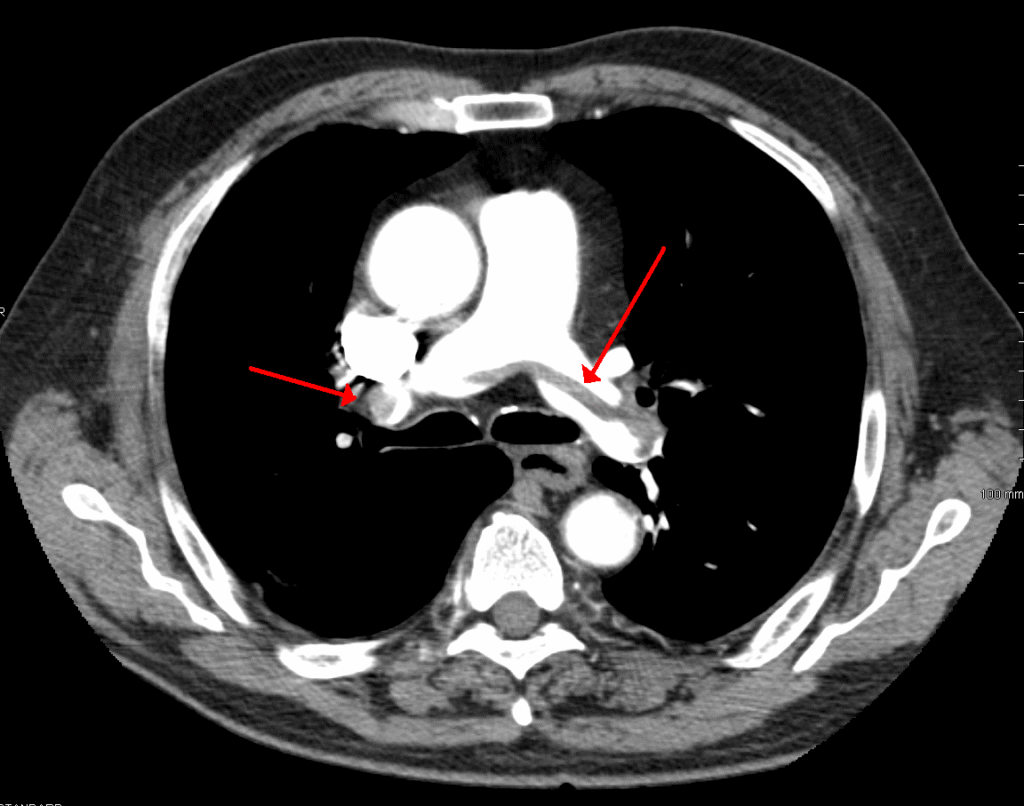

I underwent a chest x-ray (spiral CT scan), followed by an ultrasound. These revealed clots in both lungs and my left calf.